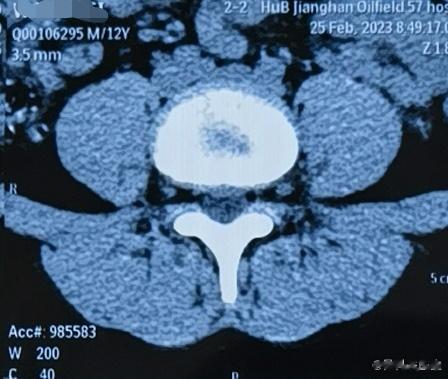

12岁的小学生都腰椎间盘突出了。久坐,缺乏锻炼。。。唉

2023-02-26 20:43